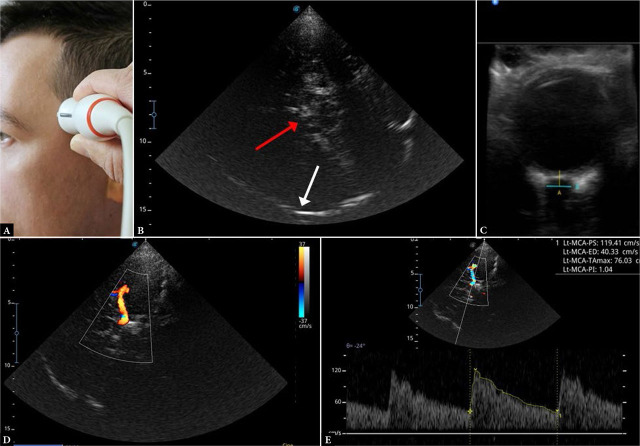

Results: POCUS-CRAFT represents five components of trauma patient evaluation. C (Cranium): Transcranial Doppler or transorbital ultrasound to assess for elevated intracranial pressure; R (Respiratory): Evaluation of the chest for pneumothorax and pleural hematoma; A (Abdomen): Evaluation of the peritoneal and pelvic cavity for free fluid; F (Cardiac Function): Diagnosis of pericardial tamponade and assessment of left ventricular systolic function; T (Trauma Integration): Integration of ultrasound findings with a complete physical examination of the trauma patient, with emphasis on the clinical context.

Abstract Image